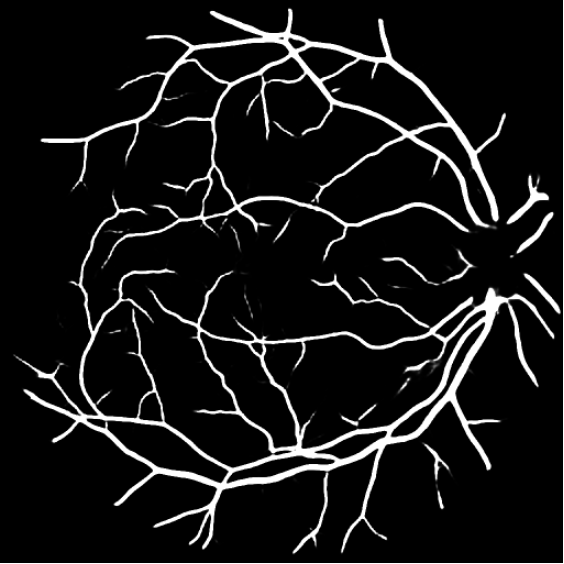

Figure 3: Qualitative results on all three segmentation tasks. The figure shows an example image, ground truth (GT) and predicted (PRED) segmentation mask for the skin lesion segmentation task (row 1), the polyp segmentation task (row 2) and retinal vessel segmentation task (row 3).

We have provided the additional qualitative results of our method for all three segmentation tasks. Fig. 5, shows the qualitative results of skin lesion segmentation, while Fig. 6 and Fig. 7, illustrate the visualization of retinal vessel and polyp segmentation tasks respectively.

Refer to caption

IMAGE

GROUND TRUTH

PREDICTED MASK

Figure 6: Visualizations of retinal vessel segmentation